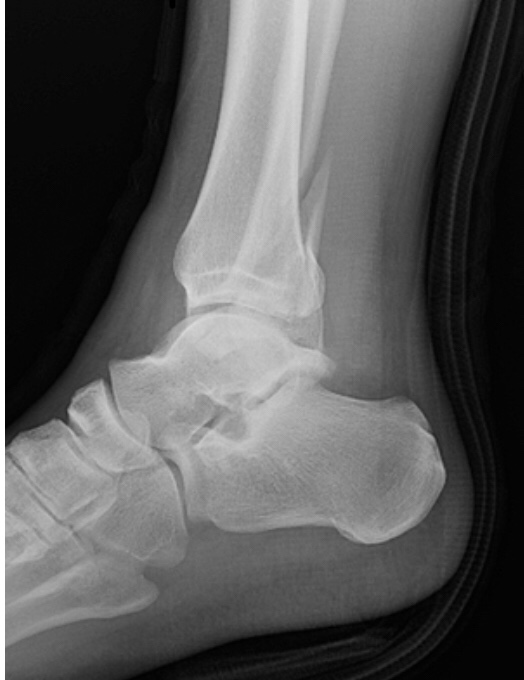

Having been taken to A&E with a mystery ailment a few months ago, Farmer Tim was struck by a far more obvious problem. Technically, he was struck by a cow falling as she, in turn, had been struck by another cow, but we won’t get into technicalities. This time, what ailed him was a rather swollen lower leg. These things tend to happen when you wrestle with a cow.

Still, he insisted that it was not broken and emphatically denied the extent of the pain until enough people strongly suggested that he have it seen. In much the same way, I denied my own arm was broken when a horse fell on it a few years ago.

Mum was right in the end, and she was also right this time: the ankle was broken. Despite having done everything he could to convince us that a trip to A&E was not necessary – including standing on it flamingo-esque in a bid to prove it wasn’t so painful after all, the large, purple haematoma on his leg refused to subside and so to the hospital he was reluctantly chauffeured by my mother. Safe in the knowledge that Farmer Tim, just like most other farmers, would not concede defeat and rest it, the doctors at A&E decided that one of these Darth-Vader-esque boots would be a better option than a cast. I must admit to going through three casts in the space of eight weeks when I smashed my arm, largely due to the muck it collected, so I can see their point. And secure in the knowledge that the boot is washable, Farmer Tim continued in almost exactly the same vein as he did before, only with a fertilizer bag over his new boot.

Unfortunately, a further visit to see his consultant left the poor man having to explain to Farmer Tim that broken limbs must be rested, and that there is a reason that any supporting structures are not waterproof. Placing a fertiliser bag over it is not a substitute for rest. Neither was he to jump off steps or climb onto the cows’ feeders in the dairy, even if it was only to show us how to fix them.